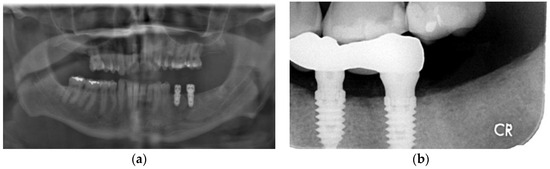

3.5. Case 5